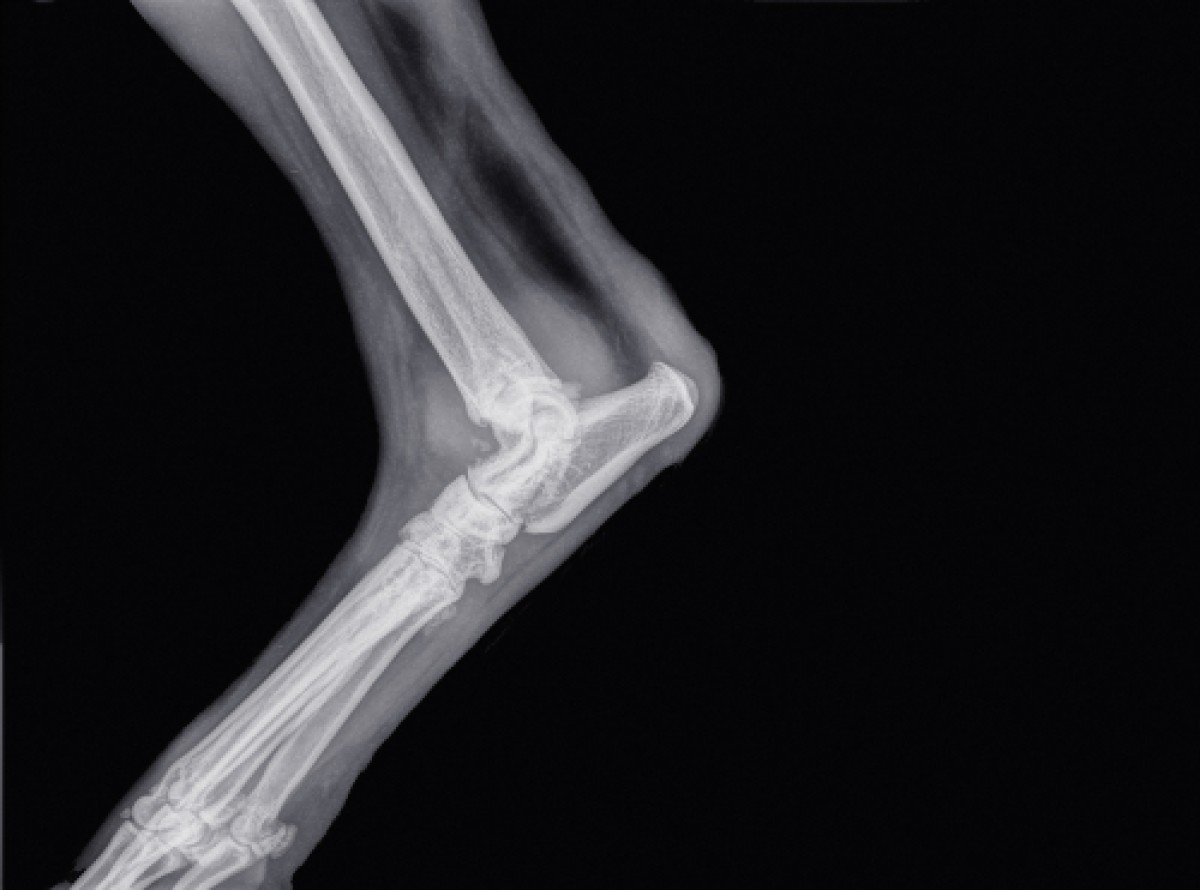

La médecine humaine et la médecine vétérinaire ont depuis toujours partagé des domaines médicaux pouvant montrer une synergie et convergence potentielles. L’arthrose mécanique (AM) est caractérisée par un déséquilibre complexe et graduel de la production, de la perte, et de la perturbation du cartilage. Toute instabilité au niveau de l’articulation provoquant une surcharge anormale de sa surface peut déclencher une arthrose mécanique. L’étiologie de ce type d’arthrose étant principalement mécanique, le traitement ne peut être efficace que si les facteurs mécaniques de l’articulation et les voies mécanosensitives altérés sont normalisés et restaurés. Dans le cas contraire, une cascade inflammatoire de l’arthrose se déclenche et peut provoquer des lésions irréversibles. La prise en charge de la pathologie par des anti-inflammatoires non stéroïdiens, des analgésiques, de la physiothérapie, des changements de régime alimentaire, ou des nutraceutiques constitue une approche plus conservatrice et moins efficace. L’arthrose mécanique est un facteur déterminant dans le développement de la dysplasie de la hanche, chez l’homme comme chez le chien. La dysplasie de la hanche est une maladie héréditaire d’incidence élevée et d’une grande importance clinique de par la gêne et les limitations fonctionnelles significatives qu’elle engendre. En outre, compte tenu des analogies de la dysplasie de la hanche chez l’homme et chez le chien et dans le cadre du concept d’une Médecine unique, l’unification de la recherche humaine et vétérinaire pourrait améliorer le bien-être et la santé des deux espèces, tout en donnant plus de visibilité à ces maladies communes. Le traitement conservateur préventif de la dysplasie de la hanche chez les hommes a connu de grands succès et, conformément au concept d’une Médecine unique, des mesures similaires pourraient également être bénéfiques pour les chiens. De plus, des modèles animaux ont très longtemps été utilisés pour mieux comprendre les différents mécanismes pathologiques. La recherche actuelle sur les modèles animaux a été examinée et le rôle des modèles utilisant le lapin dans les études physiopathologiques et des chiens comme modèle animal spontané a été souligné. Il a été conclu à l’absence de modèles fonctionnels chez les lapins pour explorer des approches thérapeutiques de l’arthrose mécanique.